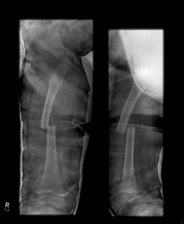

Plate

Indication

- length unstable fractures (spiral / comminuted)

- very distal or proximal fractures

- patient inability to non weight bear (cognitive impairment / developmental delay)

Options

1. Open Plating

2. Submuscular bridge plating

Technique

- supine on radiolucent table or traction table

- incision 5cm proximal or distal (depending # site)

- blunt dissection to periosteal layer

- run bristow or cobb elevator submuscularly

- 3.5 or 4.5mm LCP plate (depending on patient size and age)

- place plate submuscularly

- use stab incisions to place 3 screws above /below fracture

- sufficient spread